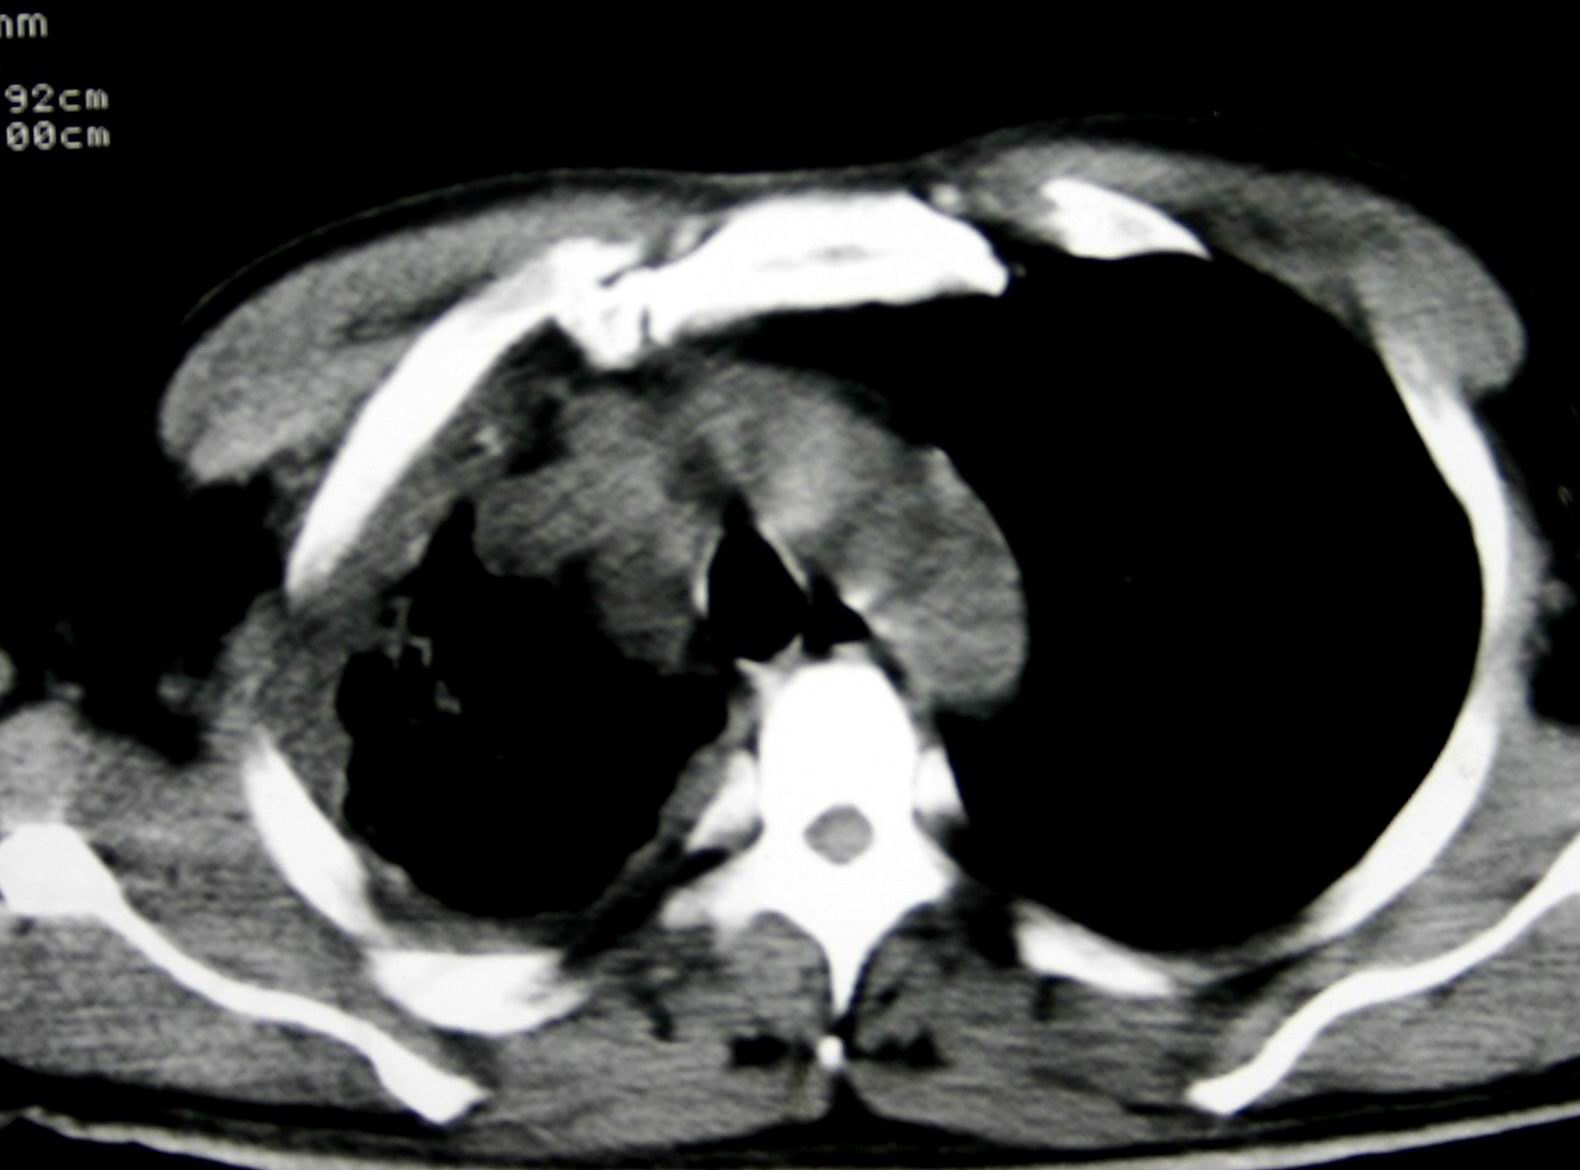

患者,男 ,48岁,反复咯血三个月,每三到五天咯一次,每次约200ml,鲜红色,无明显咳痰,咳嗽明显,无明显胸痛,无发烧,初期以抗感染、止血治疗,第一次ct报占位,支气管镜未见明显ca细,肺ca标志物、tb抗体均阴性,经过垂体后叶素、酚妥拉明、头胞他定、洛美沙星、立止血等治疗后,现病人一般情况好,停止咯血10天,咳嗽减少,咳黄脓痰,每日一次,每次30ml。现复查ct

右肺膨胀不全,纵隔右侧移位。肺内有感染,胸腔有积液。建议老片对比。

1)考虑右肺继发性肺结核合并感染。2)右侧胸腔积液+胸膜增厚。

支持:右肺膨胀不全,纵隔右侧移位。肺内有感染,胸腔有积液。建议老片对比。

感染性病变,结核可能性大,伴结核性胸膜炎。